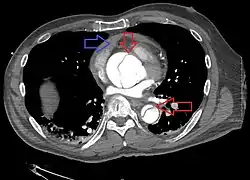

Computed tomography

Computed tomography angiography is a fast, noninvasive test that gives an accurate three-dimensional view of the aorta. These images are produced by taking rapid, thin-cut slices of the chest and abdomen, and combining them in the computer to create cross-sectional slices. To delineate the aorta to the accuracy necessary to make the proper diagnosis, an iodinated contrast material is injected into a peripheral vein. Contrast is injected and the scan performed using a bolus tracking method. This type of scan is timed to an injection to capture the contrast as it enters the aorta. The scan then follows the contrast as it flows through the vessel. It has a sensitivity of 96 to 100% and a specificity of 96 to 100%. Disadvantages include the need for iodinated contrast material and the inability to diagnose the site of the intimal tear.

Chest CT with descending (type B Stanford) aortic dissection (red circle)

Type A dissection with pericardial effusion as a result.